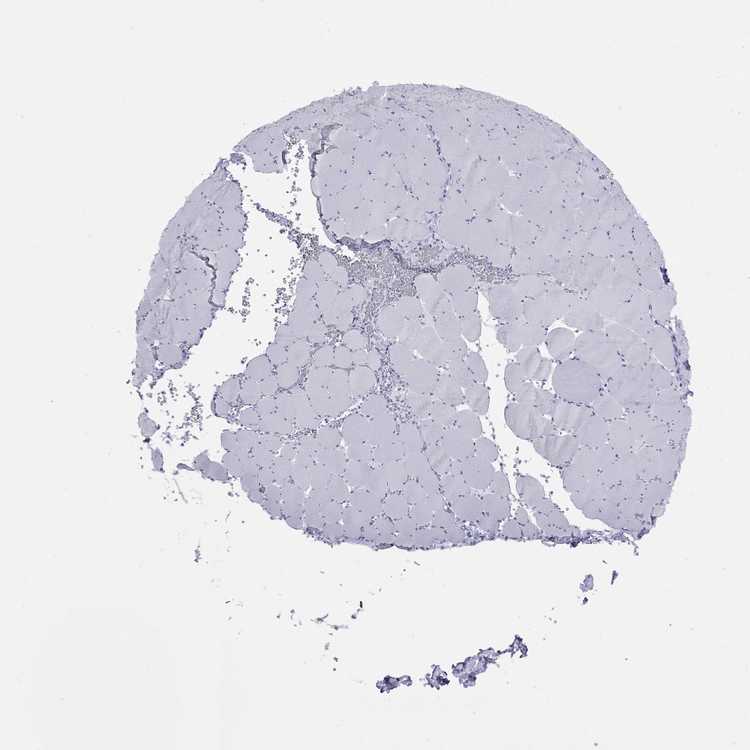

SKELETAL MUSCLE - Antibody stainingi

Antibody staining in the annotated cell types in the current human tissue is reported as not detected, low, medium, or high, based on conventional immunohistochemistry profiling in selected tissues. This score is based on the combination of the staining intensity and fraction of stained cells.

Each image is clickable and will lead to virtual microscopy that enables deeper exploration of all samples and also displays staining intensity scores, fraction scores and subcellular localization as well as patient and tissue information for each sample.

Antibody HPA035881

Myocytes Not detected